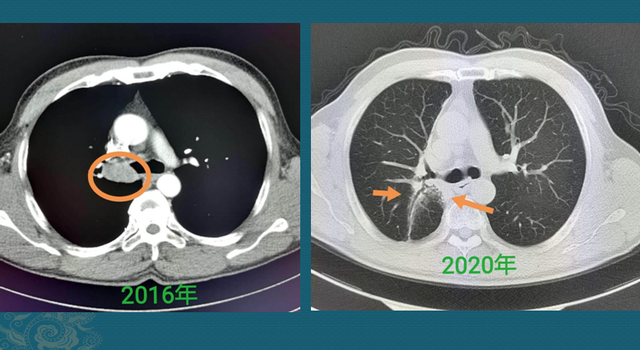

好比下面这位老烟民,由于 咳嗽、痰中带血发现右肺门肿块,支气管镜确诊为非角化型肺鳞癌:

已经无法手术切除,选择定位放疗,已经4年了状态很好,今年复查CT看到右肺门周围有一点放疗后的肺间质纤维化改变,对肺功效影响不大,没有复发征象。